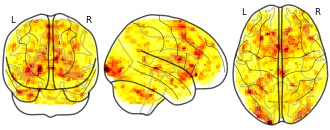

"name": "Multi_VBMsmaller_fMRIenhanced",

"description": "Multi-modal analysis in BPD. Brain regions exhibiting smaller gray matter and enhanced activation during emotion processing in BPD compared to healthy controls. Note: Results were thresholded at p<.0025. Note2: Results were updated (see Erratum for this publication).",